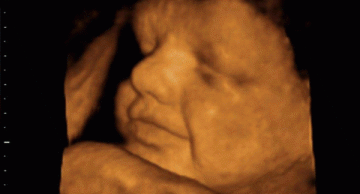

Dị tật bẩm sinh là những bất thường cấu trúc vật chất di truyền xuất hiện từ thời kỳ bào thai, tồn tại và gây ra các khuyết tật về thể chất, chức năng, trí tuệ ngay khi mới sinh hoặc có thể biểu hiện muộn hơn.

Năm 2017, Việt Nam ước tính cứ 13 phút lại có 1 em bé chào đời mang trong mình dị tật bẩm sinh. Tỷ lệ dị tật bẩm sinh ngày càng tăng lên khi sàng lọc trước sinh, sàng lọc sơ sinh trở nên phổ biến và được phổ cập trên toàn quốc. Đâu đó trong những gia đình Việt vẫn có những đứa con mang những căn bệnh quái ác từ khi sinh ra: Xương thủy tinh, dính khớp sọ, Down, Thalassemia,... khiến cha mẹ luôn phải kề cạnh ngày ngày chăm sóc, gánh nặng về vật chất và tinh thần cho gia đình cũng như cho xã hội.

Tỷ lệ trẻ sinh ra mắc hội chứng Down trên toàn thế giới là 1/700 trẻ. Trẻ bị Down có biểu hiện đặc trưng là mắt xếch, mặt phẳng, thừa da gáy, tai tròn, nhỏ, bàn tay thường chỉ có 1 rãnh chỉ tay nằm ngang. Trẻ chậm phát triển trí tuệ từ vừa tới nặng và thường có các bệnh lý tim mạch và suy giáp đi kèm.

Nguyên nhân trẻ bị Down là đột biến số lượng nhiễm sắc thể khiến mỗi tế bào thừa ra 1 NST số 21. Khoảng 5% trẻ bị Down do người mẹ có trứng mang đột biến chuyển đoạn NST 21 và NST 14, trẻ vẫn có bộ NST 46 chiếc giống trẻ bình thường nhưng có biểu hiện của hội chứng Down.

Down có thể chẩn đoán sớm từ tuần thứ 10 nhờ phân tích gen trực tiếp, tuần thứ 11 - 14 dựa vào siêu âm độ mờ da gáy kết hợp các xét nghiệm huyết thanh khác (Double test) hoặc vào tuần thứ 15 - 20 với Triple test.

Khi NIPT Illumina bắt đầu xuất hiện tại Việt Nam, nhiều chuyên gia đầu ngành khuyến cáo mẹ bầu chọn NIPT làm xét nghiệm sàng lọc trước sinh đầu tay dù đây là kỹ thuật mới, chi phí còn cao. Lý do là bởi NIPT Illumina an toàn gần như tuyệt đối với mẹ và thai nhi, cho độ chính xác >99% với trên 10 dị tật bẩm sinh thường gặp về số lượng, cấu trúc NST. Không những thế, NIPT illumina đang được nghiên cứu để tiếp cận tới những mảng tối - đột biến đơn gen di truyền trội đang là nỗi đau nhức nhối trên toàn thế giới.